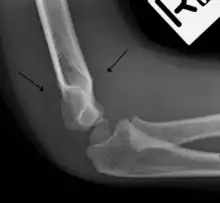

Fat pad sign

The fat pad sign, also known as the sail sign, is a potential finding on elbow radiography which suggests a fracture of one or more bones at the elbow. It is may indicate an occult fracture that is not directly visible. Its name derives from the fact that it has the shape of a spinnaker (sail).[1] It is caused by displacement of the fat pad around the elbow joint. Both anterior and posterior fat pad signs exist, and both can be found on the same X-ray.

In children, a posterior fat pad sign suggests a condylar fracture of the humerus. In adults it suggests a radial head fracture.

The fat pad sign is invaluable in assessing for the presence of an intra-articular fracture of the elbow. An anterior fat pad is often normal. However a posterior fat pad seen on a lateral x-ray of the elbow is always abnormal. The patient will be unable to flex their elbow and requires orthopaedic input.[2]

The posterior fat pad is normally pressed in the olecranon fossa by the triceps tendon, and hence invisible on lateral radiograph of the elbow.[3] When there is a fracture of the distal humerus, or other pathology involving the elbow joint, inflammation develops around the synovial membrane forcing the fat pad out of its normal physiologic resting place. This is visible as the "posterior fat pad sign" and is often the only visible marker of a fracture, particularly in the pediatrics population.